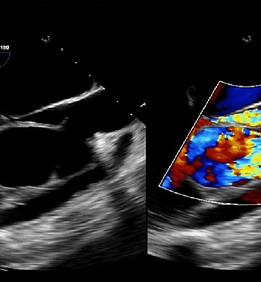

TRANSESOPHAGEAL ECHO (TEE)

We may sometimes need more detailed images of the heart than what can be produced by the standard transthoracic ECHO. TEE is used in such situations to visualize the heart. A flexible tube is inserted via the mouth into the food pipe. This probe will transmit pictures of your heart to the computer. You will be given medications to numb your throat before the procedure to minimize your discomfort. You will be allowed to have clear liquids 2 hours after this test and solids four hours later.

INTRA CARDIAC ECHOGRAPHY

We may have to perform Intracardiac Echography (ICE) during your radiofrequency ablation procedure. It aids us in complex transseptal punctures, baffle punctures and to help position the ablation catheter over the papillary muscle in papillary muscle ventricular tachycardia. The ICE catheter is inserted through a vein in the neck or the groin into the heart. It then transmits pictures through a fiber optic cable to be seen on a computer screen.